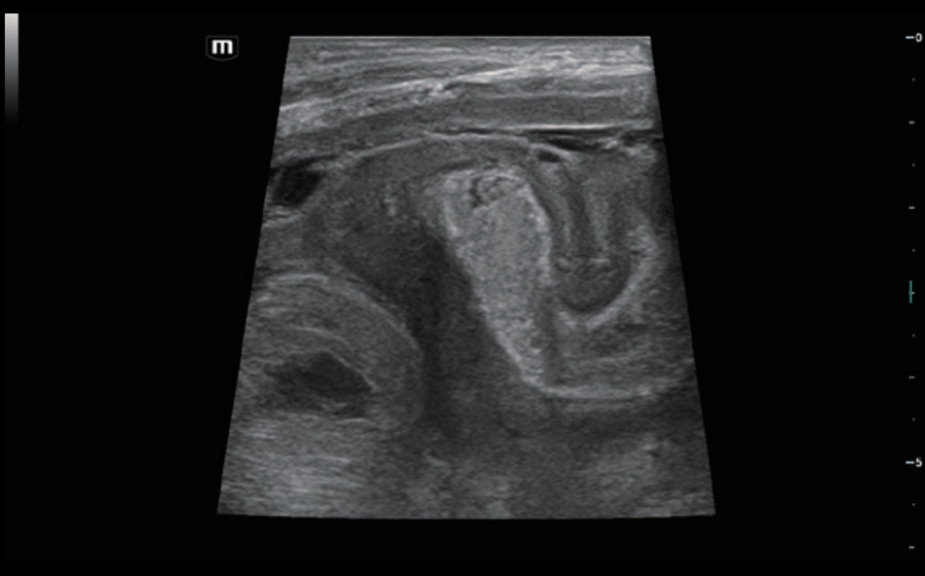

Innowacyjna Elastografia: HiFR STE

Do 10 razy szybsza cz?stotliwo?? od?wie?ania obrazu elastografii STE

Bardziej czu?e wykrywanie ruchu dla lepszej stabilno?ci i wi?kszej dok?adno?ci

HiFR STE ŌĆō nowotw├│r piesi

Innowacyjna Elastografia: HiFR STE

Do 10 razy szybsza cz?stotliwo?? od?wie?ania obrazu elastografii STE

Bardziej czu?e wykrywanie ruchu dla lepszej stabilno?ci i wi?kszej dok?adno?ci

HiFR STE ŌĆō nowotw├│r piesi